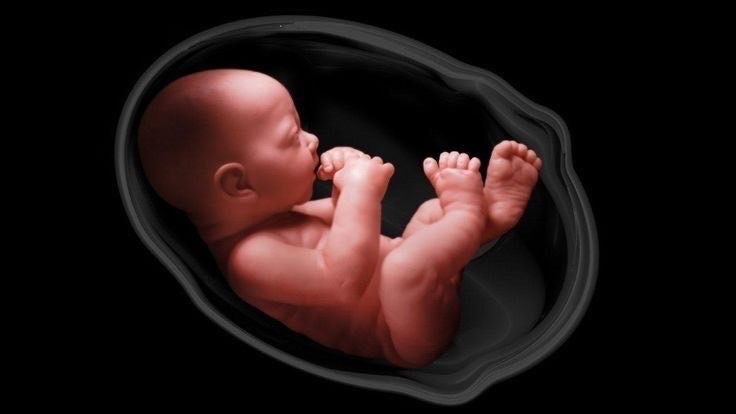

At Om Imaging Centre, we specialize in Sonography, Color Doppler, and X-ray services. Our goal is to deliver accurate and timely results, helping you and your healthcare provider make informed decisions. We strive to be the leading diagnostic imaging center in the region by offering exceptional care, advanced technology, and personalized attention.

To further refine his skills, he gained invaluable experience at State Hospital, Dharampur, and Sanjeevani Nursing Home, Talasari. A six-month observership at Synergy Imaging, Surat, and the completion of the Certificate Course in Fetal Radiology & Genetics (CCFRG) under the Indian Radiological and Imaging Association (IRIA) have fortified his expertise.